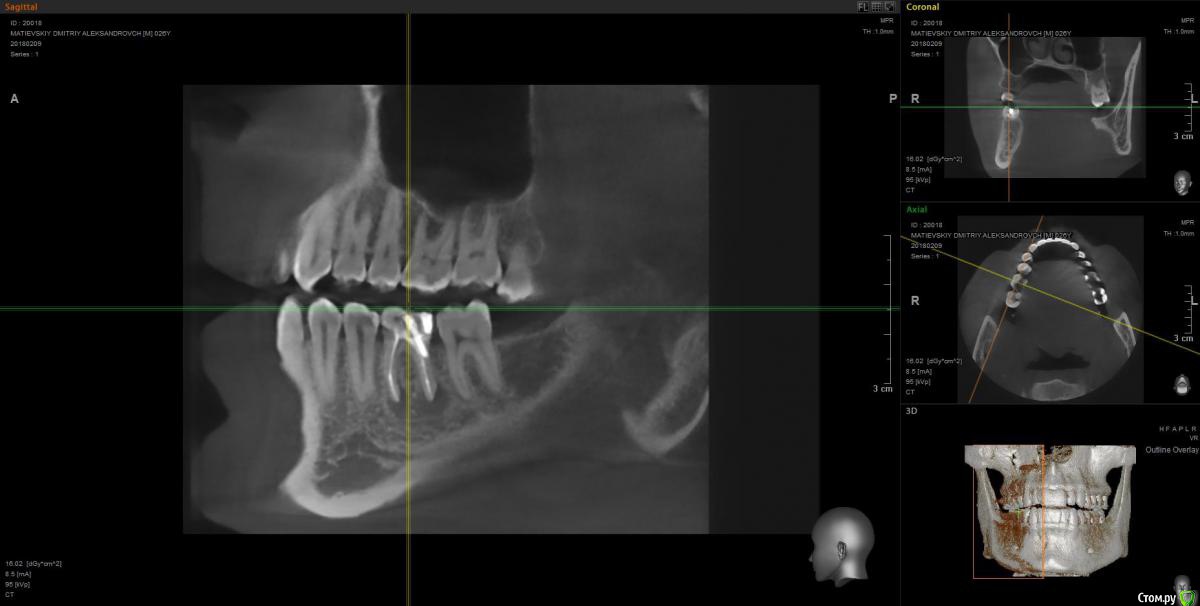

Dmitry91 Опубликовано 13 февраля, 2018 Поделиться Опубликовано 13 февраля, 2018 Добрый день, уважаемые доктора и знатоки! Прошу вашей помощи или мнения по ситуации. Есть проблемный 6й зуб на правой нижней челюсти с огромной пломбой на штифте.Внизу у корней круглые образования (кисты). Под пломбой, похоже, кариес. Стоит ли удалять зуби ставить имплант? Или есть возможность сохранить зуб? Что посоветуете? Если имплант, то какой лучше? Второй вопрос. Нужно ли удалять верхние зубы мудрости (нижних нет)? Похоже рядом с ними на 7ках естьконтактный кариес из-за того, что между зубами мудрости и 7ками застревает пища. Приложил скрины КТ и само 3D КТ в архиве, ссылка ниже. https://yadi.sk/d/kfX43ds43SMxCo Если нужно посмотреть фото с другой стороны, могу сделать. Кто поможет, заранее спасибо!) Ссылка на комментарий

Irouil Опубликовано 13 февраля, 2018 Поделиться Опубликовано 13 февраля, 2018 Удалять восьмерку (вижу только одну) - ОБЯЗАТЕЛЬНО! Удалять шестёрку? Я перспективы лечения не вижу. Какой имплант ставить? Самый надёжный, без оглядки на эстетику. Ссылка на комментарий

DmitrySH Опубликовано 13 февраля, 2018 Поделиться Опубликовано 13 февраля, 2018 ? Или есть возможность сохранить зуб? Если хотите гарантий, то удаляйтеЕсли есть желание сохранить зуб, то можно перелечить. Очаги воспаления скорее всего пройдут, но зуб будет достаточно хрупкий и ненадежный. Соответственно без гарантии. А по стоимости примерно равносильно имплантации Ссылка на комментарий

колесников Опубликовано 14 февраля, 2018 Поделиться Опубликовано 14 февраля, 2018 6ка удаляется. Желательно одномоментно поставить Имплант. Рекомендую Astra tech. Из дополнительных манипуляций будут:формирователь,0,5г костного материала, пластика десны. Верхняя восьмерка ,с этой стороны , так же удаляется. Ссылка на комментарий